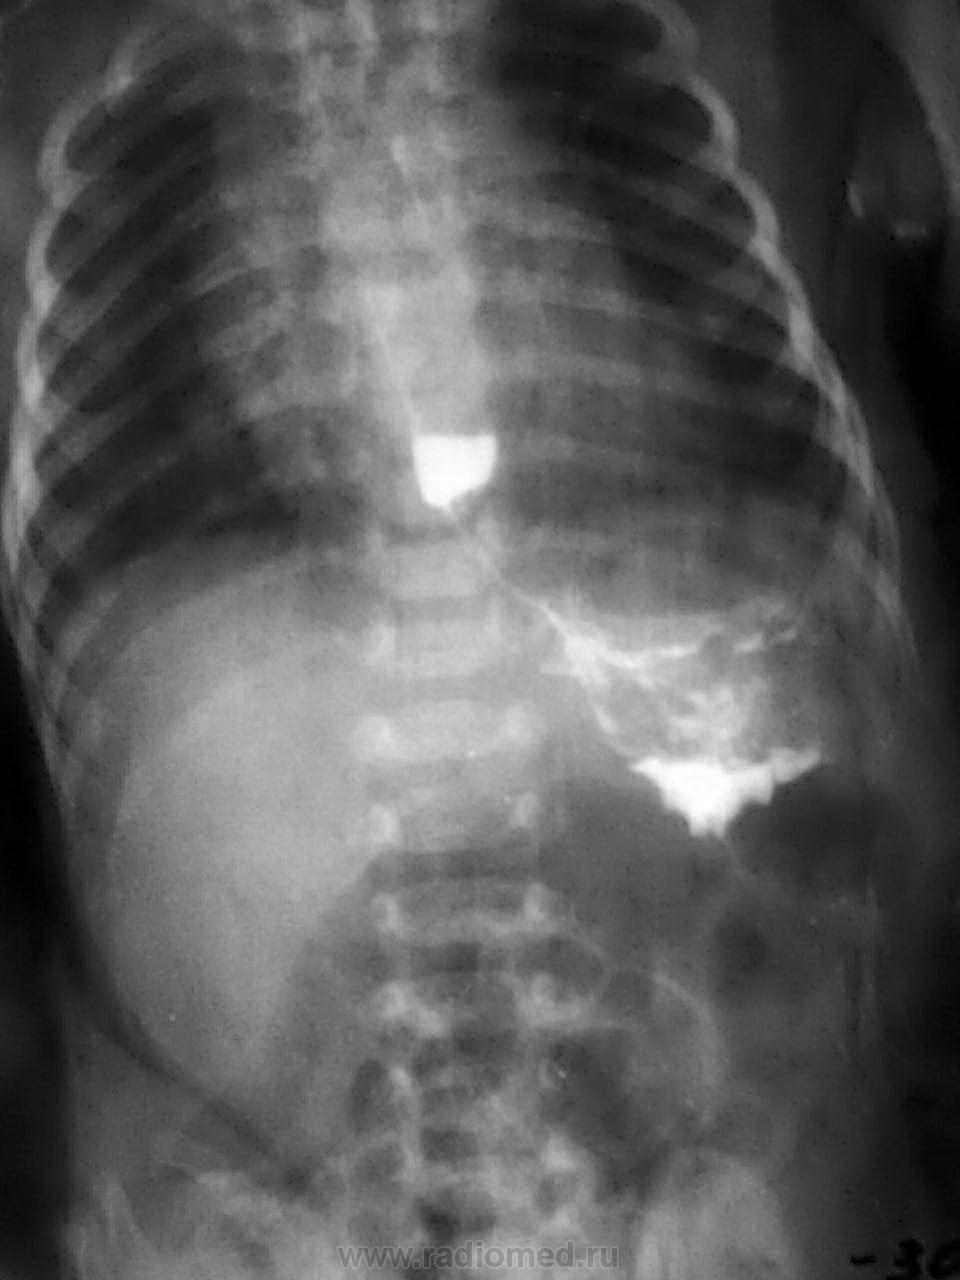

3 недели после рождения. Рвота после кормления.

-установили зонд

- подвесили

- контрастное вещество-барий

-динамика в течение 6 часов

-заключил:р-признаки ахалазии пищевода, пилоростеноза

Конечно, до месяца надо использовать только водорастворимый контраст. То есть через 6 часов барий еще в желудке, в кишечнике нет? Тогда, скорее всего, пилоростеноз.